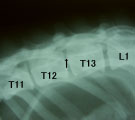

初診時。後肢の対麻痺。ほとんど随意運動なし。 脊髄造影。T12-T13間の背側で充填欠損像あり。 手術所見。脱出した髄核の摘出前(上)と後(下)。 術後2週間で自分で立ちながら食事を食べられるようになった。

経過:受診時、後肢の対麻痺あり、ほとんど随意運動なかった。痛覚認知あり尾運動は認められた。椎間円板ヘルニアが疑われた。まず入院で内科療法を2日間試みたが次第に尾運動がなくなってきたので、外科的減圧術を考慮して脊髄造影を行った。T12-T13の椎体間背側に充填欠損が認められ、他の部位には異常なかった。そこでこの部位の片側椎弓切除術を行った。術中、脱出した髄核が脊髄を圧迫していることが分かりそれを全て摘出した。術後経過は良好であり、2週間後には自分で立って食事を食べれるようになった。